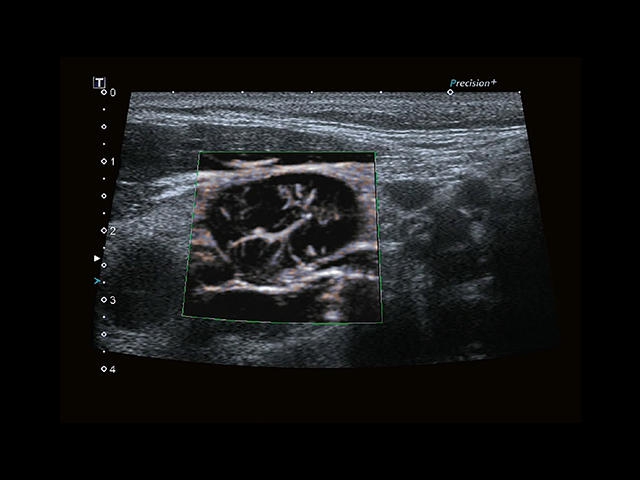

Обновленная версия легендарного УЗ-сканера. Стационарный аппарат экспертного класса Aplio 500 Toshiba NEW, визуализирует анатомические структуры в высоком разрешении. Модель позволяет выявить микрокальцификаты, новообразования, нарушения в работе сердца, сосудов и мышц. Присутствует функция виртуальной эндоскопии, 4D-сканирования, эластометрии тканей, УЗИ с контрастированием. За повышение качества изображения отвечают технологии ApliPure и Superb Microvascular Imaging. Первая задействует возможности пространственного и частотного кодирования, формирует цельный визуальный ряд с сохранением клинических маркеров. Вторая улучшает отображение микрососудистого русла, используя доплеровский эффект. Модель оснащена 21-дюймовым монитором, имеет 4 активных порта. Возможно подключение педиатрических, интраоперационных, лапароскопических и чреспищеводных датчиков.

- MicroPure. Высокотехнологичное решение в области выявления микрокальцификатов – маркеров новообразований злокачественного типа. Маркеры идентифицируются путем изучения затененных изображений целевого участка. Микрокальцификаты отображаются в виде белых пятен.